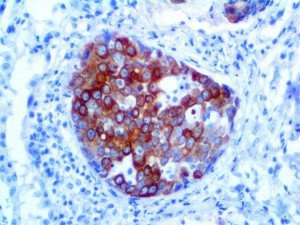

It is the ICU physician who is most likely to witness one of the deadliest manifestations of the abnormal immunological response, the cytokine storm syndrome (CSS). This response is also referred to by some as the cytokine release syndrome (CRS). CSS is characterized by continuous activation and expansion of macrophage and lymphocyte populations, which secrete large amounts of cytokines, causing the cytokine storm. This massive cytokine release is akin to hemophagocytic lymphohistiocytosis (HLH) disease, a syndrome characterized by initial unchecked and persistent activation of cytotoxic T lymphocytes and NK cells.

Clinical and laboratory manifestations of HLH include fever, enlarged liver and/or spleen, neurologic dysfunction, coagulopathy, liver dysfunction, cytopenias (i.e., low levels of erythrocytes, leukocytes, and/or platelets), hypertriglyceridemia, hyperferritinemia, hemophagocytosis, and eventually diminished NK cell activity as the immune system becomes progressively paralyzed. HLH can be familial (primary HLH) or secondary to another disease process (sHLH), such as rheumatic disease, in which it is referred to as macrophage activation syndrome (MAS, characterized by elevated ferritin).